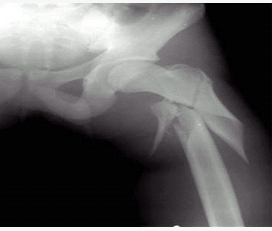

病史:男性,35岁,外伤30分钟。诊断:()

A:右胫骨骨折

B:左髋关节脱位

C:左股骨骨折

D:右腓骨骨折

E:右胫骨骨折